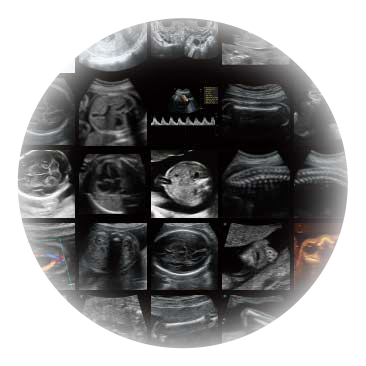

临床图